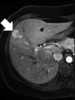

Liver lesion with central scar